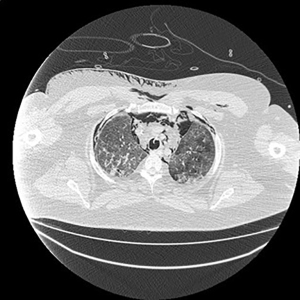

Electronic patient dataset provided checking anamnestic information. All records of the patients included were evaluated with the Hungarian patient-specific (Health Insurance Number coded) electronic database. The analysis was secured by full anonymization protocol. As far as the CT images are concerned, tissue free areas within the pleural space and mediastinal and/or pericardial collection with free air density have been graded. Bullae, pneumokele, fluid-free lung cysts less than 10% of the relevant lobe were categorised as stage I, destroyed lung, covering >50% of the ipsilateral hemithorax were categorised as stage III underlying destructive lung pathology. All positive cases between stages I and III were considered as stage II destructions. PTX less than 20% of ipsilateral lung surface was Grade 1 (Figure 1), while total PTX and those subtotal ones causing tension PTX were categorised as Grade 3. Any extension of free air collection between Grade 1 and 3 was categorised as Grade 2. The PM group was treated as a separate entity (Figure 2). Iatrogenic PTX was excluded from the study.